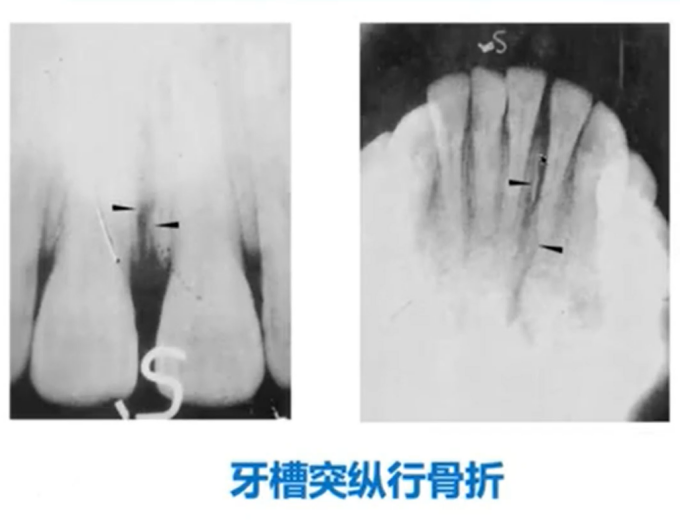

三、牙齿发育异常:1、牙体形态异常2、牙体结构异常3、牙齿数目异常4、阻生牙5、牙周炎6、牙外伤